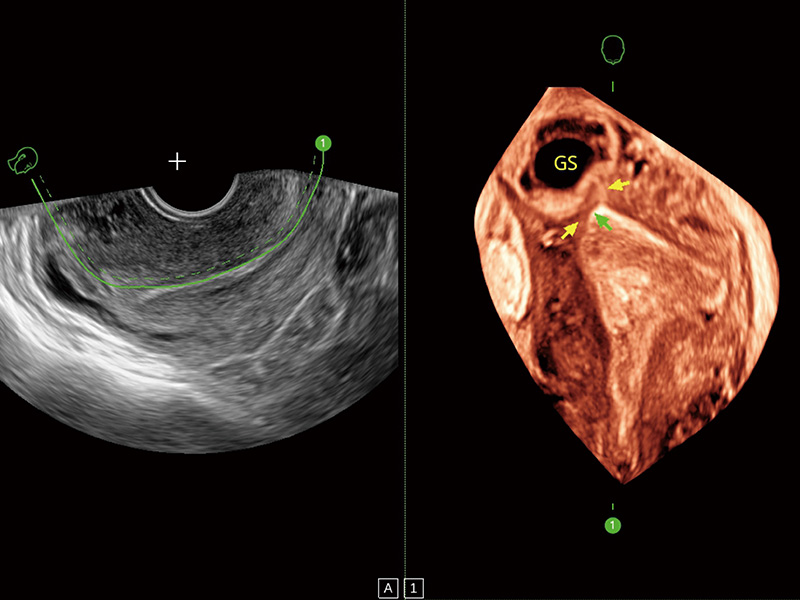

“生育问题”即关系民族复兴,也关系亿万家庭的幸福。随着婚育年龄推迟、社会压力增加等因素,越来越多人群也面临着“生不出、生不好”的问题。辅助生殖作为治疗不孕不育最有效的方法之一,也逐渐成为育儿新希望。而超声检查能为生殖需求人群的初诊评估提供宝贵的信息。 P20 Elite是db真人体育官网匠心打造的一款生殖应用型彩超。她继承db真人体育官网高端极光平台,突破性地将多款新型芯片及硬件模块进行整合,均衡了高端系统性能与小巧灵动机身。P20 Elite卓越的图像质量搭载专科探头,旨在为您提供全面的辅助生殖解决方案。

P20 Elite配备了丰富的生殖探头群和临床应用功能,在卵泡监测、穿刺取卵、胚胎移植、妊娠确认等领域,为生殖需求人群提供了新的临床机会,重新定义高端超声如何应用于生殖健康检查。

通过线上云会诊平台,实现县级医院与上级医院患者卵泡数据互联互通。避免重复性卵泡测量,提高诊断效率。